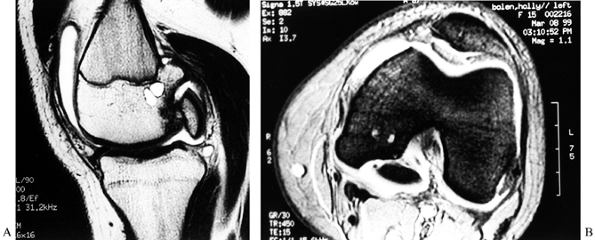

MRI can accurately predict the size of the lesion. The OCD lesion can

be staged, because MRI will demonstrate whether or not a breach has

![]() |

Figure 84.31. CT (A) and MRI (B) of an osteochondritis dissecans lesion of the medial femoral condyle.

accurately with the MRI classification. The MRI findings, in

conjunction with the arthroscopic findings, are often necessary to

determine the treatment that is indicated for each individual OCD